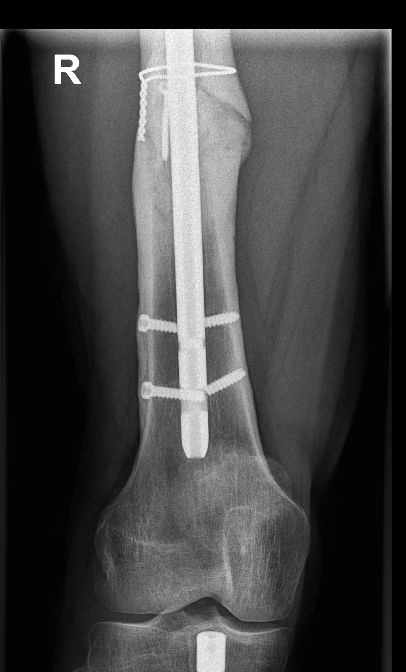

Today’s monteggia brought to you by the CCCP

#orthosky

#orthopedics